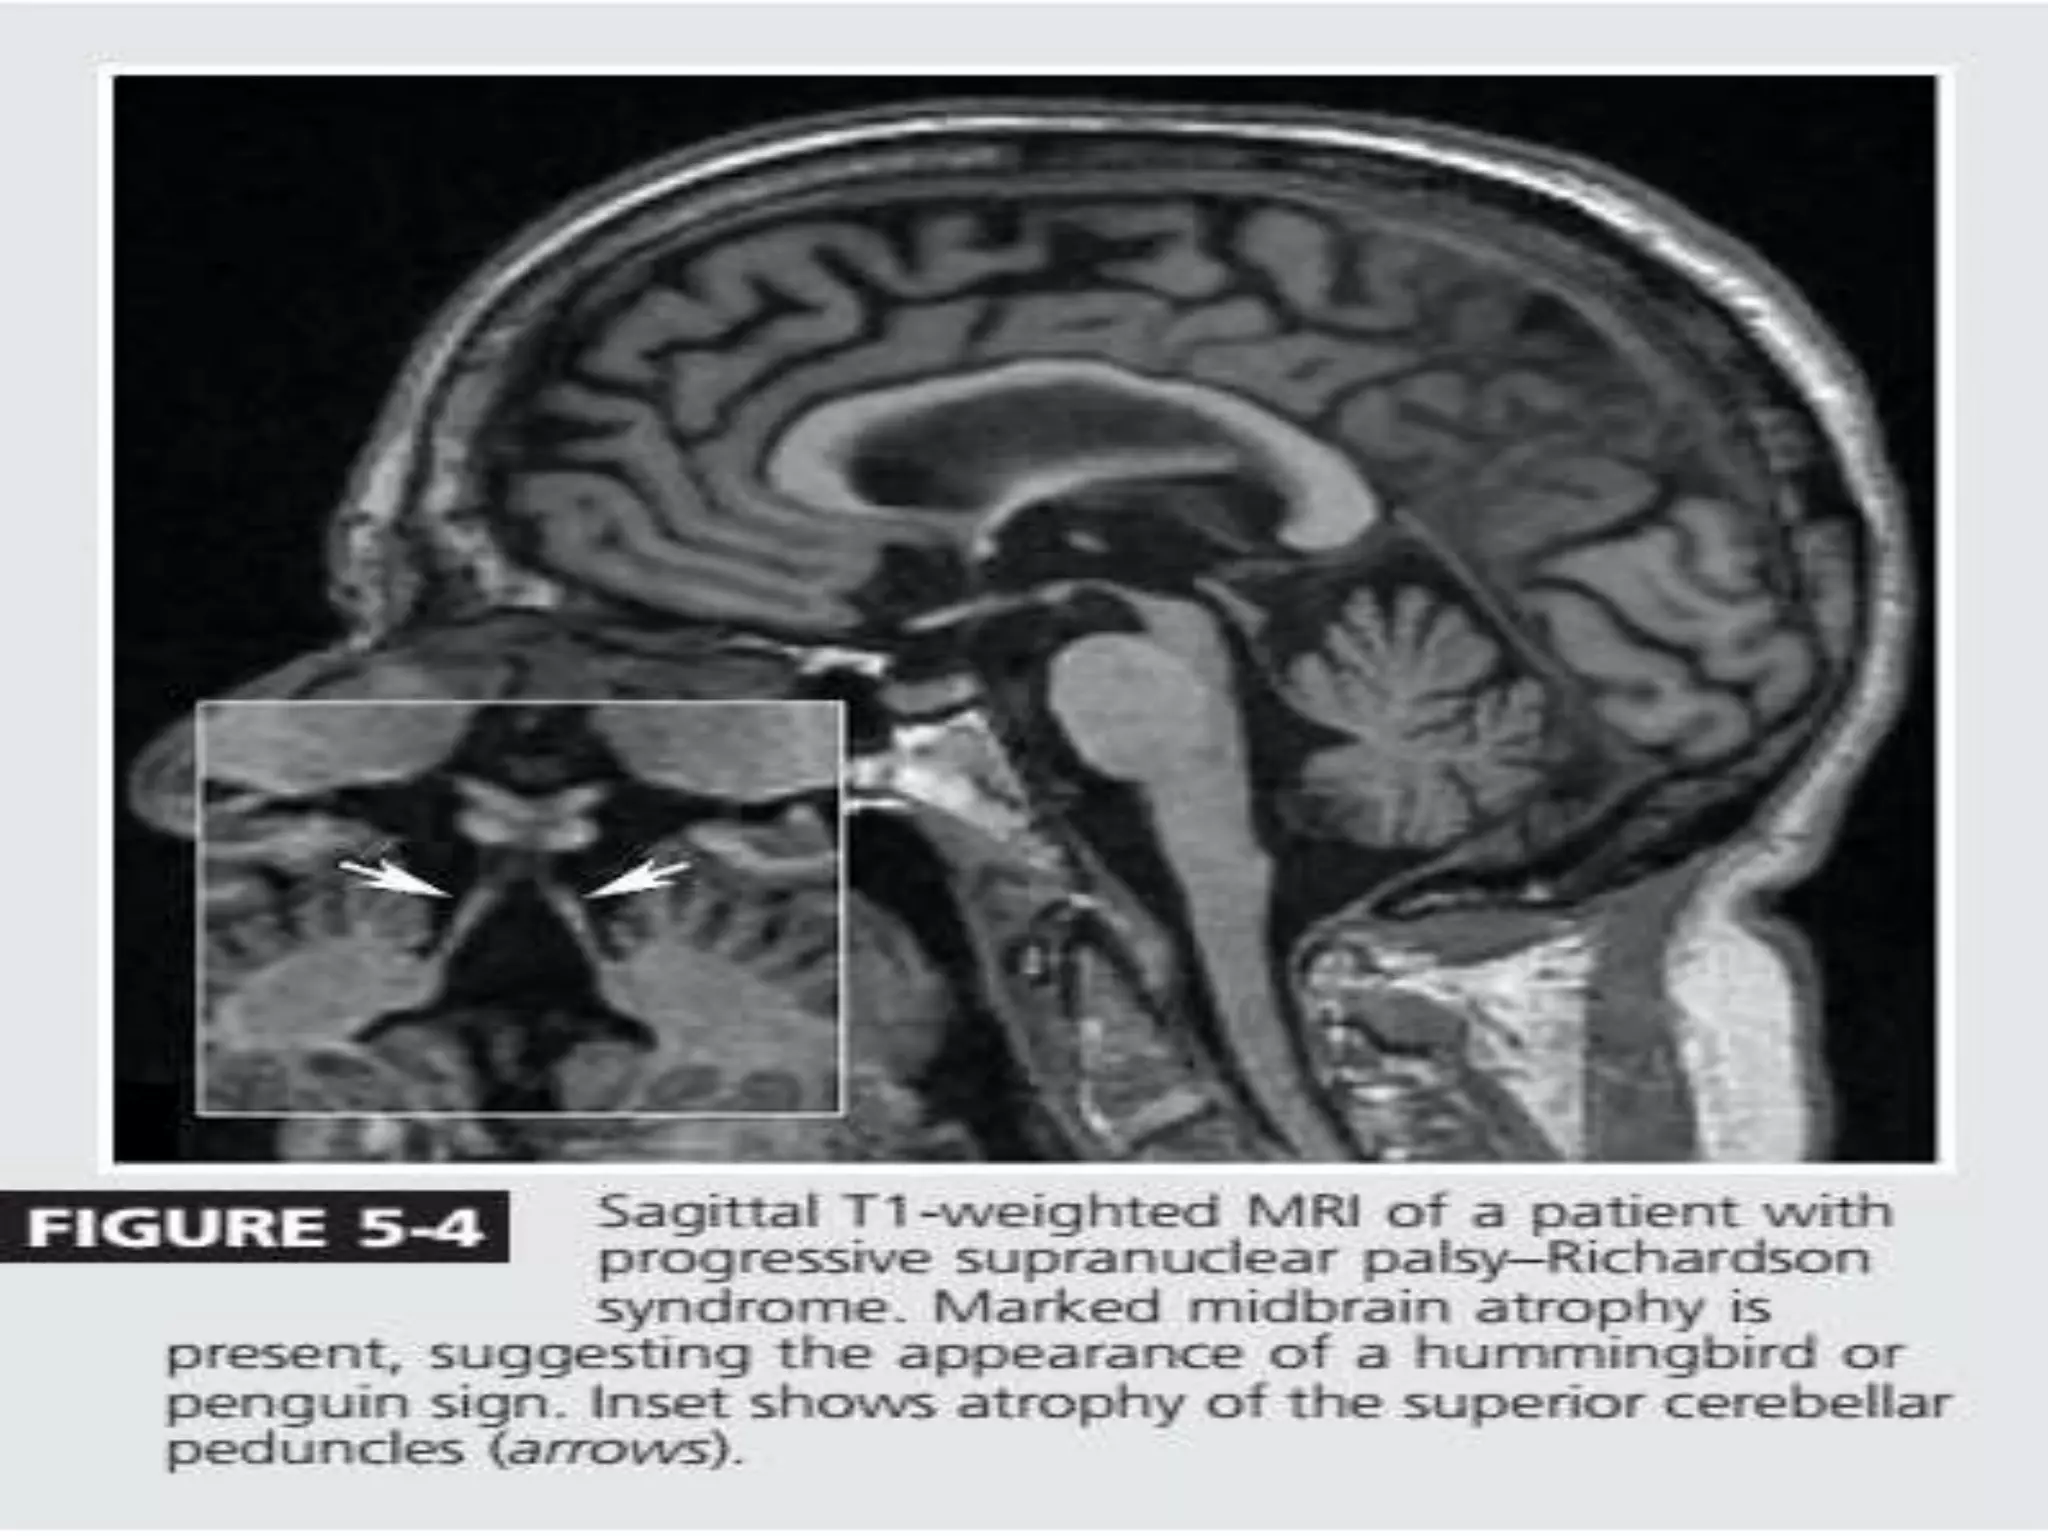

• MRI midbrain atrophy (appearance of a flat or concave profile

-68% sensitivity and an 89% Specificity

• Superior cerebellar peduncle atrophy.

• “Morning Glory Flower Sign” and the “Hummingbird Sign” –

Highly specific(100%) low Sensitivity (50% and 68.4%)